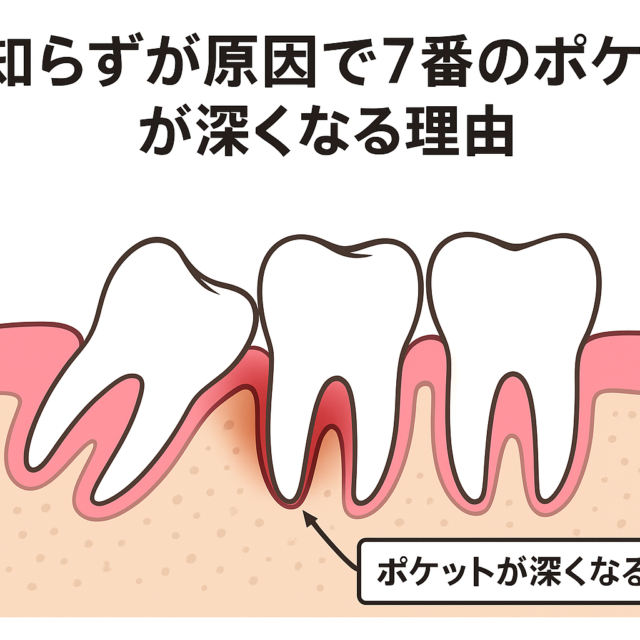

歯周病は、サイレントディジーズ(silent disease:静かなる病)とも呼ばれるほど、なかなかご自分では気付きにくい病気です。

歯周病の症状としては

- 歯茎から出血する(膿が出る)

- 歯茎が赤く腫れている

- 口臭が気になる

- お口の中がネバネバする

- 歯がグラグラする

- 硬いものが痛くて噛めない

- 歯と歯の間に食べ物が挟まりやすい

- 歯が長くなったように感じる

などが挙げられます。

歯石取りをしても、骨にまで感染が及んでいる場合、骨の再生は自然には起こりません。部分的(垂直的)に骨が吸収されている場合、数年で歯を失う確率が高くなります。